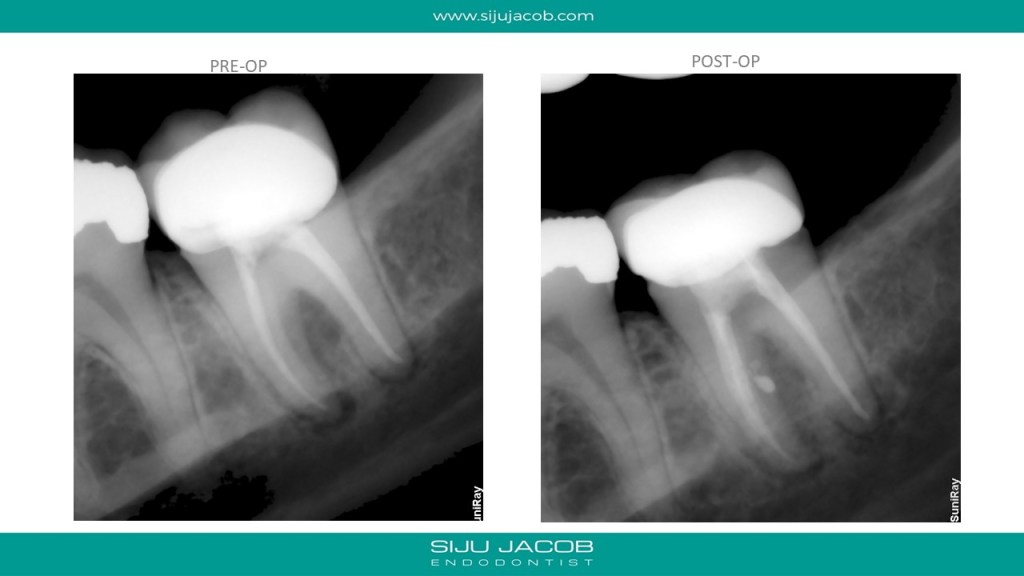

In the past, when we attempted Re-treatment, we used to re-treat all the canals. For the past 4-5 years, I’ve been doing mostly selective Re-treatment ie: treat only those roots or canals which need something to be done. Michael Trudeau calls it “Titrated Treatment”. Some of my friends call it “Image guided Treatment (IGT)”.

This patient had pain on a previously endo treated and crowned mandibular second molar. CBCT showed a missed mesio-lingual canal. I decided to Re-treat the Mesio-buccal canal as well because the CBCT scan showed that the missed mesio-lingual canal merged with the mesio-buccal canal apically.